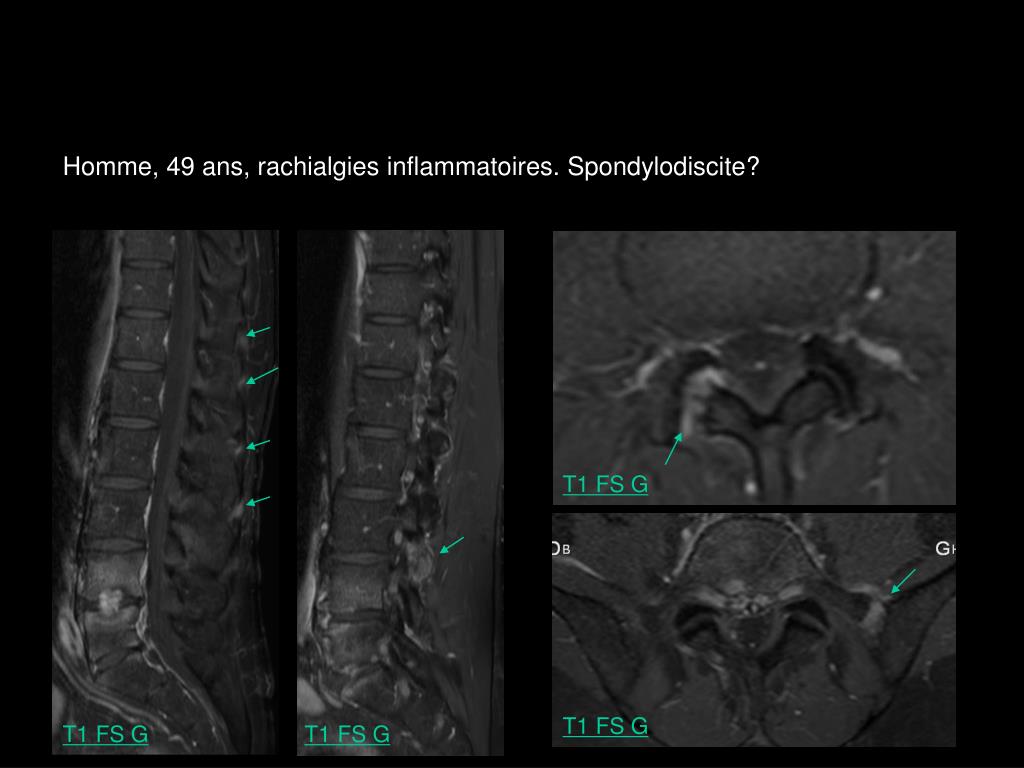

5. Homme, 49 ans, rachialgies inflammatoires. Spondylodiscite? T1 FS G STIR T2 TSE T1 FS G

6. Homme, 49 ans, rachialgies inflammatoires. Spondylodiscite? T1 FS G T1 FS G T1 FS G T1 FS G